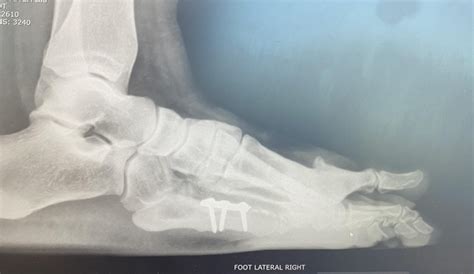

Synthetic Grafts Will Replace A Damaged Talus Bone Of The Foot

Why use synthetic bone grafts?